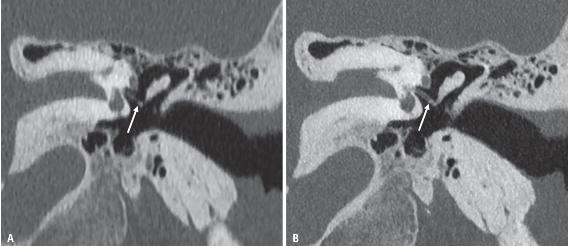

空间分辨率发挥非常重要作用的另一个感兴趣领域是小骨结构成像,特别是颞骨。Benson等人研究表明, PCD的空间分辨率提高了关键解剖结构(如砧板关节)、假体和病理的可视化(图4)。

图4 在EID-CT(A)和PCD-CT(B)图像上显示的砧板关节(箭头)。

该关节是使用5点Likert评分特别分级的几种解剖结构之一,更高的评分说明PCD-CT图像的质量更好。